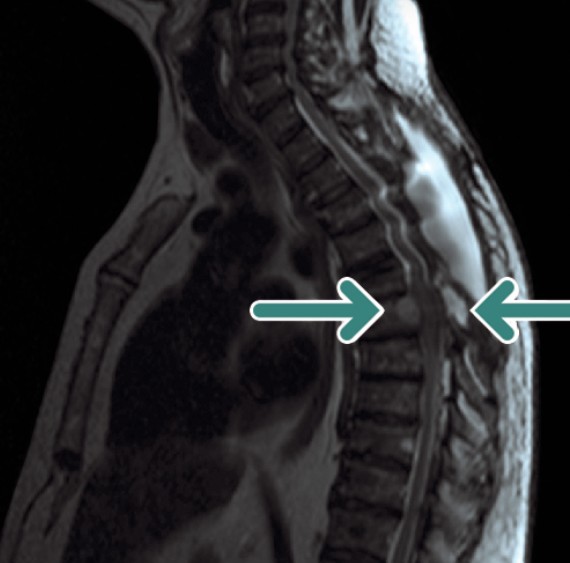

Sindrome da compressione midollare

Questa sindrome è causata dalla compressione del midollo spinale o della cauda equina da parte di una massa tumorale. Rappresenta un’emergenza assoluta, poiché un ritardo diagnostico-terapeutico può portare a lesioni neurologiche permanenti. I tumori primitivi che più frequentemente la causano sono quelli del polmone e della mammella.

Il quadro clinico di presentazione include:

- dolore (90% dei casi): tipicamente localizzato a livello della colonna, peggiora con i movimenti e il decubito e risponde scarsamente agli analgesici comuni;

- perdita di forza (70%): si manifesta con debolezza, solitamente bilaterale e simmetrica, a livello degli arti;

- alterazioni della sensibilità: presenti nel 50-70% dei pazienti, anche se raramente sono un sintomo d’esordio;

- alterazioni autonomiche: la perdita del controllo sfinterico (ritenzione o incontinenza urinaria) è un segno tardivo e indica una prognosi infausta.

La diagnosi è primariamente clinica. La Risonanza Magnetica Nucleare (RMN) è la tecnica di imaging di elezione per confermare il sospetto e definire l’estensione della lesione.